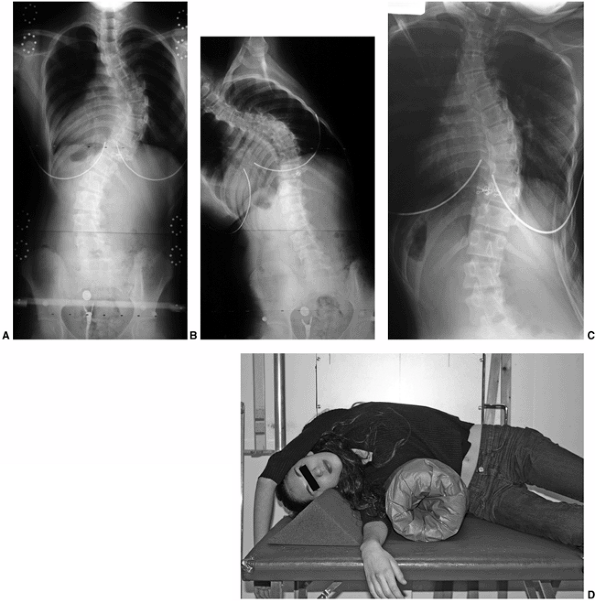

Figure 18.12 A:

This standing-position preoperative posteroanterior radiograph demonstrates right thoracic scoliosis with moderate left lumbar scoliosis. B: The flexibility of the left upper thoracic and left lumbar curves was assessed via the left-side-bending radiograph. C: The flexibility of the right thoracic curve was evaluated using the bolster side-bending technique. D: The bolster side-bending film is taken with the trunk laterally flexed on a bolster positioned under the ribs that correspond to the apex of the deformity.  |